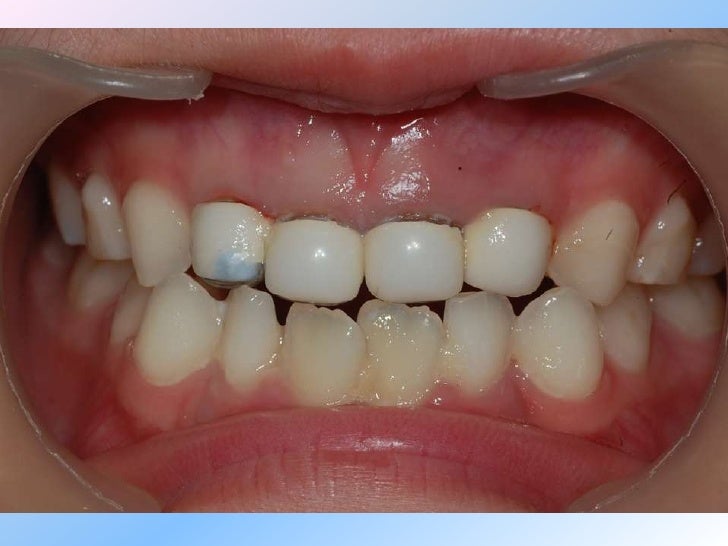

Pediatric zirconia crowns Changing pediatric restorative dentistry

Pediatric zirconia crowns Changing pediatric restorative dentistry Zirconia Crown Slideshare The document outlines the various uses of zirconia in dentistry including crowns, bridges, implants, and more. It also discusses challenges with bonding to. The included studies reported that zirconia crowns for primary teeth were associated with better gingival and periodontal health, good. Monolithic zirconia primary crowns advantages • lifelike esthetics to rival custom laboratory fabricated crowns • proven durability in. Zirconia Crown Slideshare.